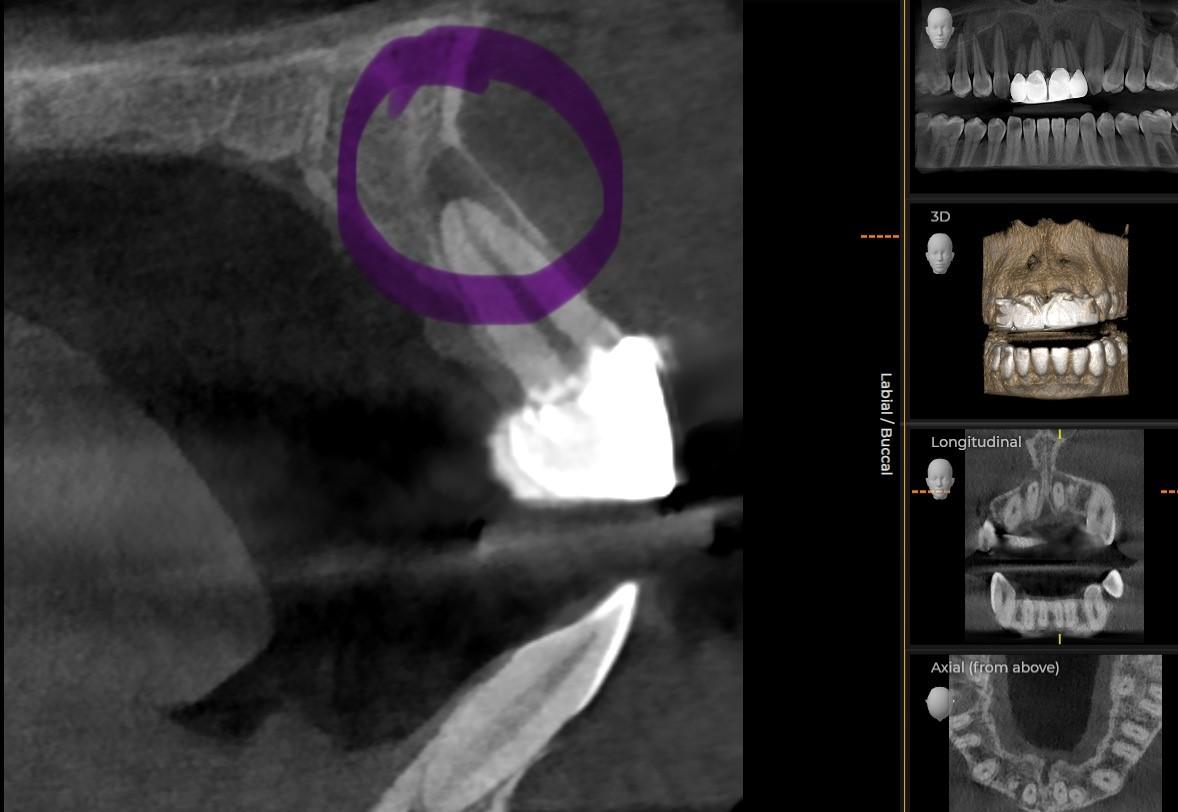

CBCT Scans London: Why they are a Game-Changer in Dentistry At Optimal Dental Health, we’re always striving to stay at